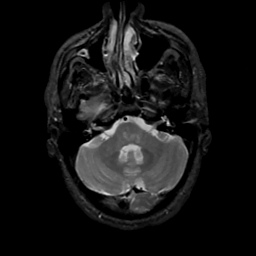

MR Study #4, March 3, 1991 -- Slice #11

[Home][Help][Clinical][Tour 1][Tour 2] Slice 11